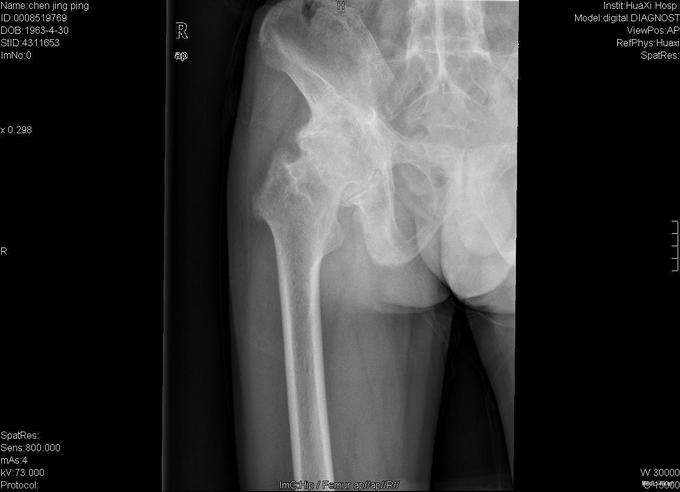

查体:跛行步态,强迫体位,脊柱强直后凸畸形,活动受限。右髋强直畸形,压痛、叩痛,无瘢痕、窦道,无皮损、皮癣,活动受限。双下肢感觉无明显异常。 辅助检查:x线片:脊柱呈"竹节样"改变,腰椎小关节间隙模糊,双侧骶髂关节及右髋关节间隙消失,骨性融合。

诊断:强直性脊柱炎 右髋关节强直 治疗:完善相关检查后在全麻下行右侧全髋关节置换术+髋臼成形术,手术顺利,术后予以抗炎+抗凝+阵痛等治疗。